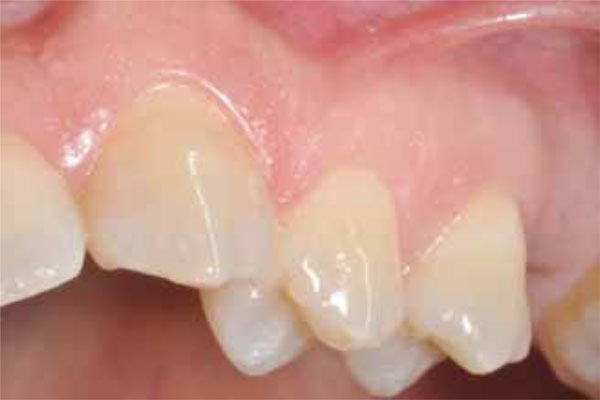

The patient noticed the presence of a painless red swelling on the vestibular gingiva of the left maxillary bicuspid region by four months. At that time, the lesion had showed a slow nodular growth. (Fig. 1).

Fig. (1).

Intraoral photograph of soft tissue mass located on the vestibular gingiva in the left maxillary premolars area.

Intraoral photograph, taken thirty months after surgery: here, the healed vestibular gingiva without any tumor recurrence is shown.